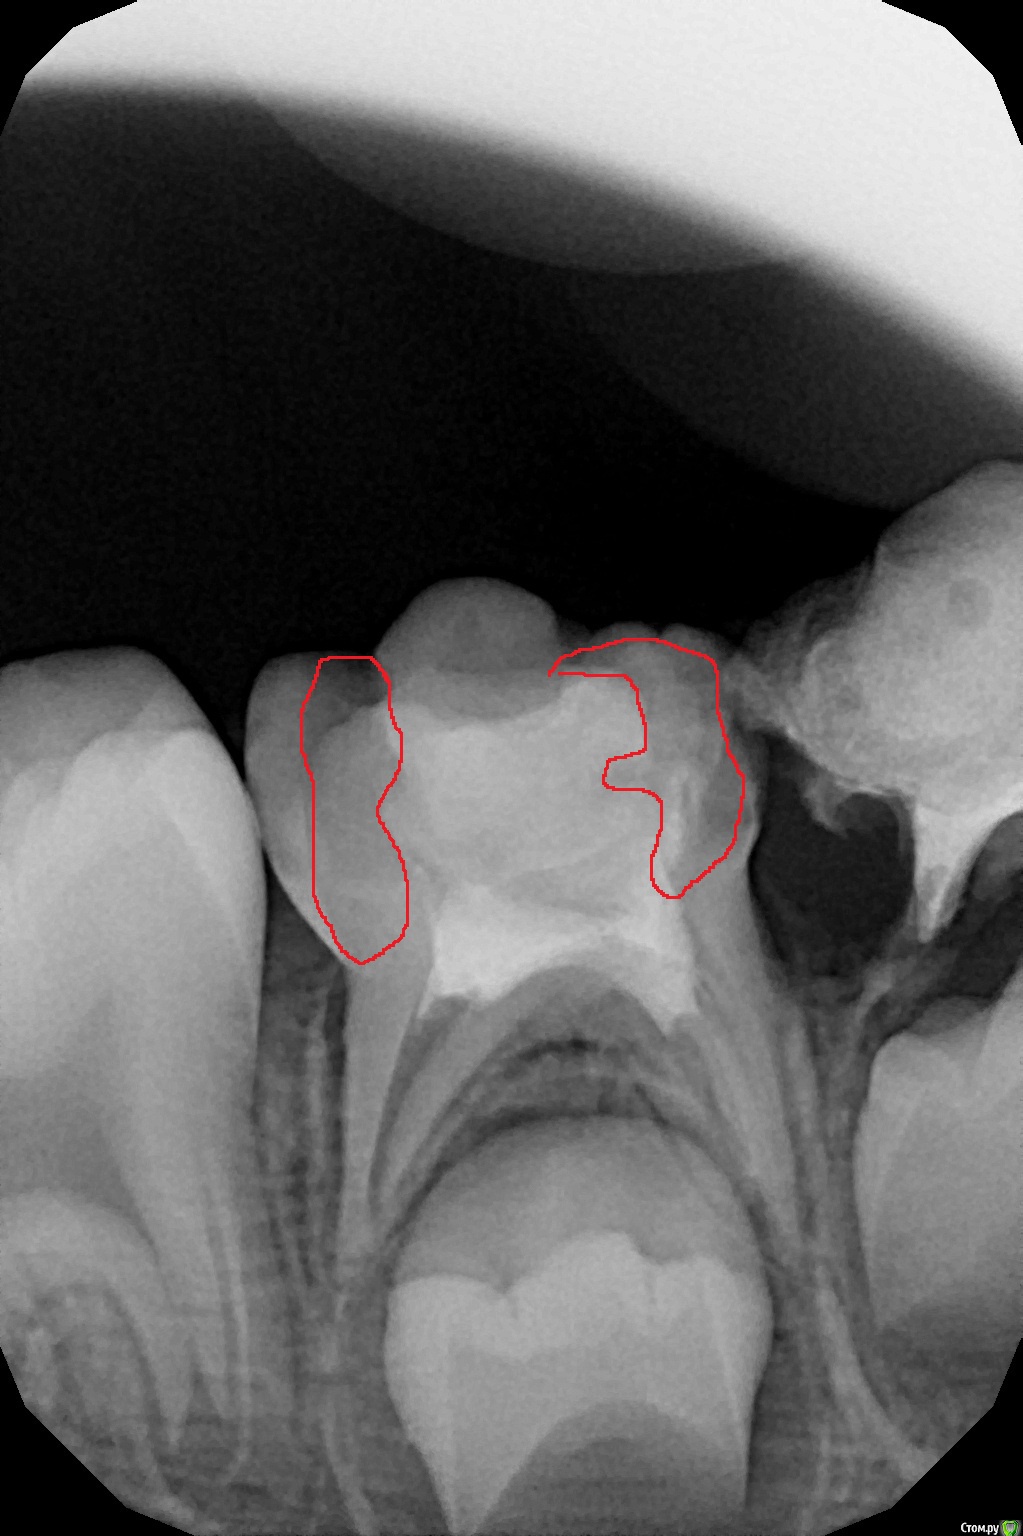

crown Опубликовано 16 июня, 2016 Поделиться Опубликовано 16 июня, 2016 (изменено) Елена вот лепешка из СИЦа, апроксимальные стенки полностью разрушены и так уже не один год, зуб лечен рф методом. Где воспаление? Джима как меньше сделать снимок, а то он гигантский открывается на форуме? Изменено 16 июня, 2016 пользователем crown Ссылка на комментарий

ЕленаВалерьевна Опубликовано 16 июня, 2016 Поделиться Опубликовано 16 июня, 2016 Елена вот лепешка из СИЦа, апроксимальные стенки полностью разрушены и так уже не один год, зуб лечен рф методом. Где воспаление? значит из сица не лепешка, а пломба)а где стенки разрушены? вроде нет, особенно дистально много тканей сохранено Ссылка на комментарий

crown Опубликовано 16 июня, 2016 Поделиться Опубликовано 16 июня, 2016 (изменено) значит из сица не лепешка, а пломба)а где стенки разрушены? вроде нет, особенно дистально много тканей сохраненоЭто область некротизированного и размягченного дентина. Вобщем огрызок, пломба в середине. Изменено 16 июня, 2016 пользователем crown Ссылка на комментарий

Джима Опубликовано 17 июня, 2016 Поделиться Опубликовано 17 июня, 2016 да.а зачем меньше снимки? так лучше видно crown, я не уверена, что на том снимке огрызка так уж всё благополучно. изменения там есть. но бог знает, за счёт чего, организм нашёл равновесие, и зуб бессимптомный. если в таком виде, не лазя внутрь, попробовать сверху всё вычистить и накрыть коронкой, думаю, он рванёт. 1 Ссылка на комментарий